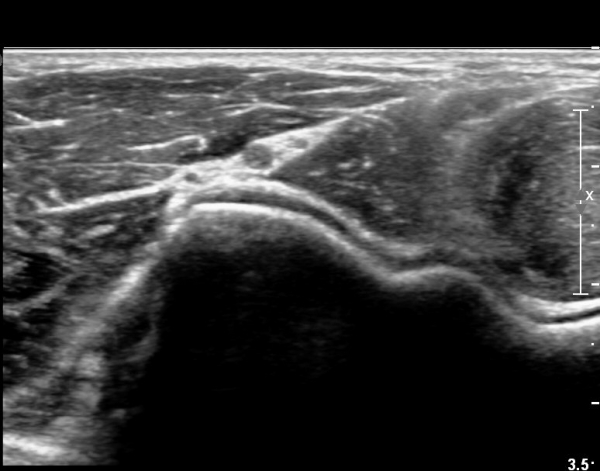

ŽÃËÀÚ¸¦ ¸»´ÜÀ¸·Î Á¶±Ý À̵¿ÇÏ´Ï Èİñ°£ ½Å°æÀÌ ÀÛ¾ÆÁö°í(»çÁø 2),